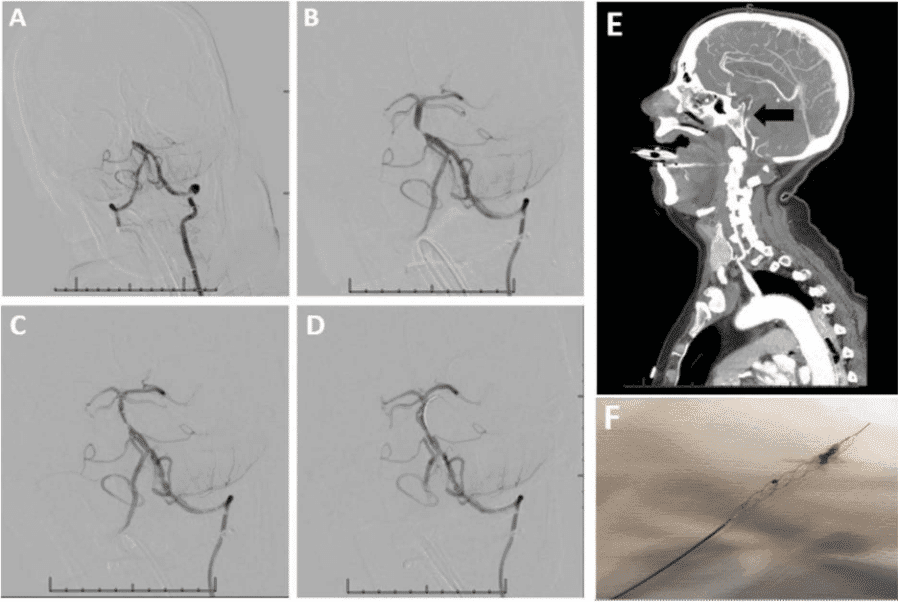

(A) Angiografia de subtração digital (DSA) de um trombo oclusivo no terço médio da a. basilar, distal à AICA. (B) Imagem DSA pós-trombectomia mecânica com um retrievable stent revelando uma estenose basilar subjacente. (C) Imagens DSA pós-angioplastia da estenose. (D) Imagens DSA pós-stent e angioplastia da estenose basilar média. (E) AngioTC demonstrando a oclusão basilar média, seta preta. O suprimento arterial ao topo da a. basilar era fornecido pela artéria comunicante posterior direita. (F) Trombo preso no stent após a trombectomia mecânica.